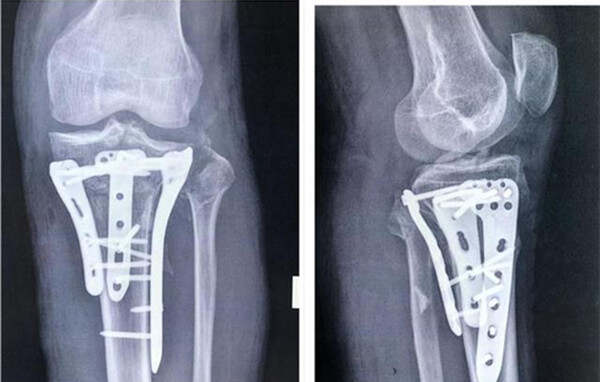

今年68歲的羅爹爹,因車(chē)禍導(dǎo)致頭部、左膝部受傷,入院診斷:硬膜外血腫、左脛骨平臺(tái)粉碎性骨折(SchatzkerⅥ型)、左腓骨小頭骨折??紤]該患者年齡大,合并腦部損傷,骨折粉碎嚴(yán)重,為縮短手術(shù)時(shí)間、提高效率和手術(shù)質(zhì)量,該院骨科主任楊俊忠提出了用3D打印技術(shù)輔助手術(shù)治療,制定手術(shù)方案,精準(zhǔn)治療。

數(shù)字化設(shè)計(jì)結(jié)合3D打印技術(shù),打印出了受損的脛骨、腓骨、股骨模型。在楊俊忠?guī)ьI(lǐng)下骨科創(chuàng)傷關(guān)節(jié)專(zhuān)家組成員副主任醫(yī)師胡浩、副主任熊家亭、醫(yī)師黃攀、黃傳文進(jìn)行了術(shù)前的討論,根據(jù)模型精準(zhǔn)了解骨折類(lèi)型,設(shè)計(jì)手術(shù)切口、預(yù)演術(shù)中步驟、內(nèi)植物的安放位置及術(shù)中復(fù)位技巧,制定出可行的治療方案,手術(shù)按照計(jì)劃進(jìn)行,術(shù)后的康復(fù)也令人滿(mǎn)意。